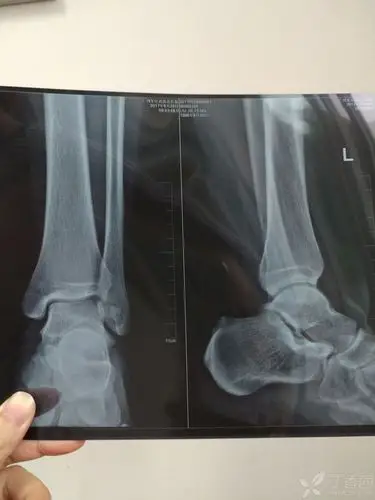

踝关节正侧位